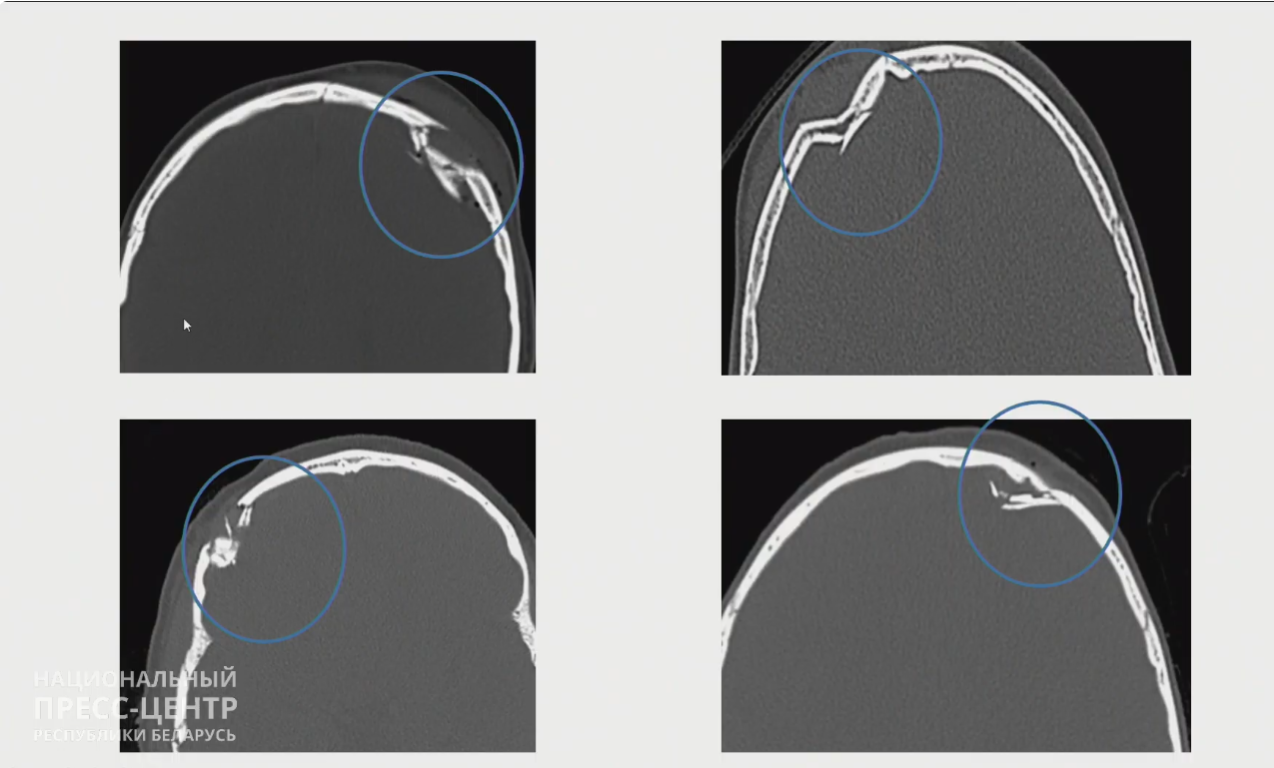

Типичная травма – перелом черепа, который сопровождается повреждением головного мозга.